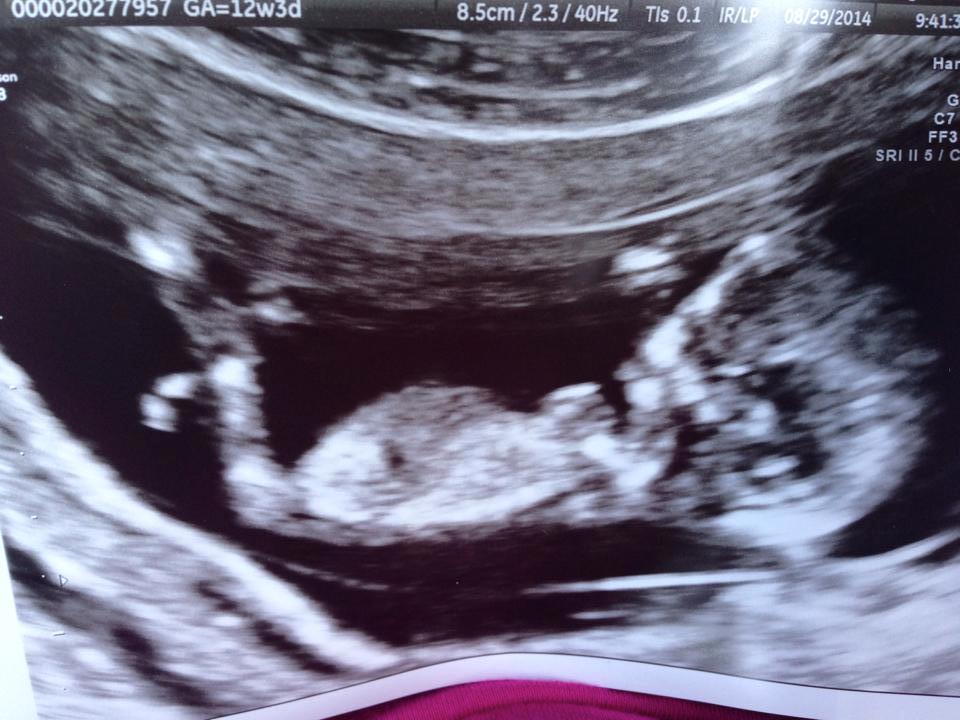

She's 12w2d and had an unexpected US today - she is having her NT scan tomorrow so hopefully gets much better pics but figured if we can post these here today why not? Any guesses??? THANKS!

Attachment 20620